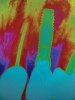

In this case, a dental implant that had been placed 10 years prior was functional, stable, and esthetically acceptable to the patient. However, a significant fistula was present on the facial-apical aspect of the ridge in the maxillary lateral incisor area. This area was painfully sensitive to touch and demonstrated purulence when squeezed. To evaluate the lesion, first, a conventional digital radiograph was acquired, which revealed an apical radiolucency at the apex of the implant (Figure 1). Further analysis using cone-beam computed tomography (CBCT) demonstrated a fistula from that site to the oral environment (Figure 2). Treatment options were discussed, including removal of the implant, followed by grafting, a healing period, and replacement of the implant and implant-retained crown. If this option was selected, a transitional appliance would need to be created. Another option was to attempt to salvage the implant and implant crown by treating the infection and grafting the site to create a new boney wall and eliminate the fistula. Ultimately, the patient accepted this option to attempt to salvage the fixture and crown.

(2.) Preoperative CBCT analysis demonstrating a fistula from the site of the radiolucency to the oral environment.

Figure 2